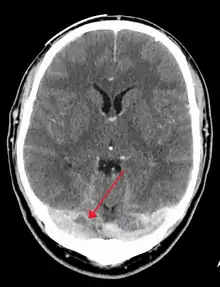

There are various neuroimaging investigations that may detect cerebral sinus thrombosis. Cerebral edema and venous infarction may be apparent on any modality, but for the detection of the thrombus itself, the most commonly used tests are computed tomography (CT) and magnetic resonance imaging (MRI), both using various types of radiocontrast to perform a venogram and visualise the veins around the brain.[3]

Computed tomography, with radiocontrast in the venous phase (CT venography or CTV), has a detection rate that in some regards exceeds that of MRI. The test involves injection into a vein (usually in the arm) of a radioopaque substance, and time is allowed for the bloodstream to carry it to the cerebral veins – at which point the scan is performed. It has a sensitivity of 75–100% (it detects 75–100% of all clots present), and a specificity of 81–100% (it would be incorrectly positive in 0–19%). In the first two weeks, the "empty delta sign" may be observed (in later stages, this sign may disappear).[11] The empty delta sign is characterized by enhancement of the dural wall without intra-sinus enhancement.[6]

Magnetic resonance venography employs the same principles, but uses MRI as a scanning modality. MRI has the advantage of being better at detecting damage to the brain itself as a result of the increased pressure on the obstructed veins, but it is not readily available in many hospitals and the interpretation may be difficult.[11]